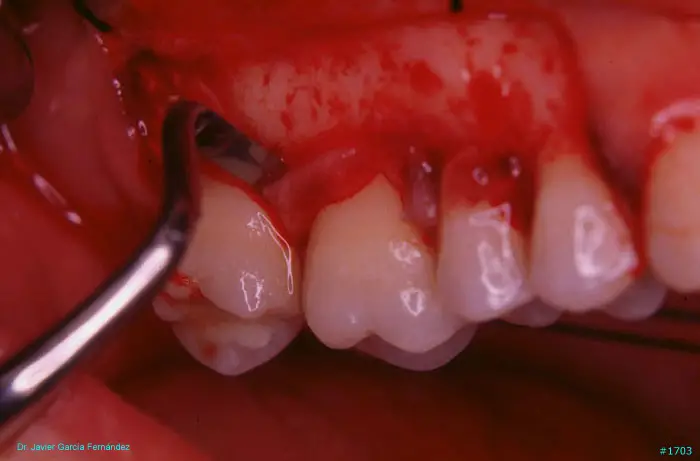

Atlas of Surgical Techniques in Periodontics. Chapter IV. Atlas de Técnicas Quirúrgica en Periodoncia

image 214